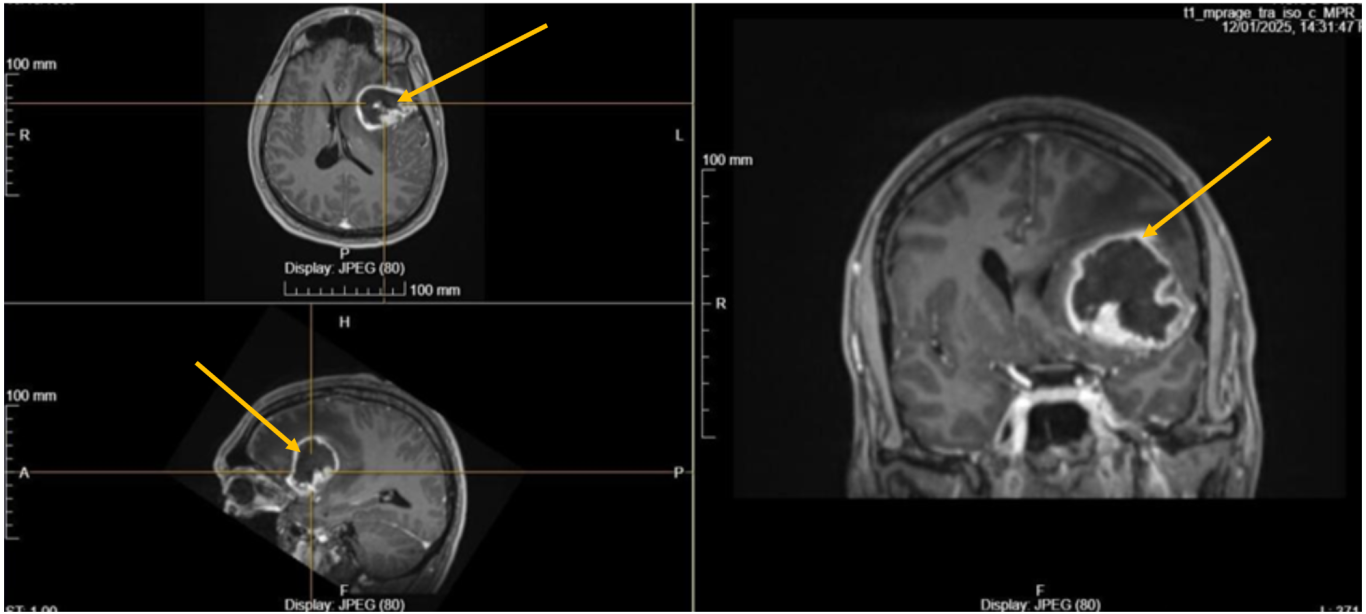

Κλινικό παράδειγμα:

Νεαρός ασθενής (39 ετών) με διάγνωση γλοιοβλαστώματος (1η εικόνα), το οποίο αφαιρέθηκε χειρουργικά.

Ο ασθενής έλαβε μετεγχειρητική ακτινοθεραπεία για 6 εβδομάδες (2η εικόνα) σε συνδυασμό με χημειοθεραπεία.

Τι έδειξε ο δεύτερος απεικονιστικός έλεγχος

Μετά την ολοκλήρωση της συνδυασμένης ακτινο-χημειοθεραπείας (ακτινοθεραπεία σε συνδυασμό με τη χημειοθεραπεία) - και ενώ ο ασθενής συνέχιζε τη χημειοθεραπεία - η μαγνητική τομογραφία έδειξε μικρή εστία υποτροπής σε περιοχή του εγκεφάλου απομακρυσμένη από την αρχική εστία και το πεδίο της ακτινοθεραπείας (3η εικόνα).

Εικόνα 1: Μαγνητική τομογραφία εγκεφάλου: εκτεταμένο γλοιοβλάστωμα (4,6Χ3,2Χ4,2) εκ. στον αριστερό μετωπιαίο λοβό του εγκεφάλου.

Εικόνα 2: Μετεγχειρητική ακτινοθεραπεία με τεχνική VMAT

Εικόνα 3: απομακρυσμένη υποτροπή (πράσινο βέλος). Τα κίτρινα βέλη δείχνουν την χειρουργική κοιλότητα μετά την αφαίρεση του αρχικού όγκου.